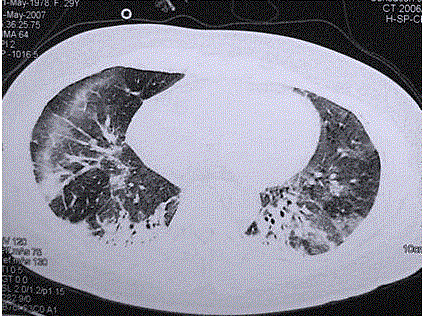

问题 患者女,29岁。间断干咳10年余,加重4个月,伴进行性呼吸困难1个月。病程中出现双手及双足非凹陷性肿胀、双侧膝关节及双侧肘关节对称性肿痛,面部出现细小红色丘疹。体检:T 36.5℃,P 88次/min,R 22次/min,BP 110/75 mmHg,SpO 93%(自然)。额部、前胸及后背散在红色小丘疹,双肺呼吸音增强,双肺中下肺野可闻及爆裂音,右肺明显。胸部CT 如图所示。 下一步处理包括(提示 肺泡灌洗液细胞分类:巨噬细胞41%,淋巴细胞58% ,分叶核细胞1%,经皮肺活检为NSIP富细胞型。)

选项 A.病理诊断已经明确,直接治疗 B.开胸肺活检 C.皮肤活检 D.检测抗核抗体 E.检测肌酶谱 F.皮肤活检 G.J0-1抗体 H.痰找瘤细胞

答案 CDEFG